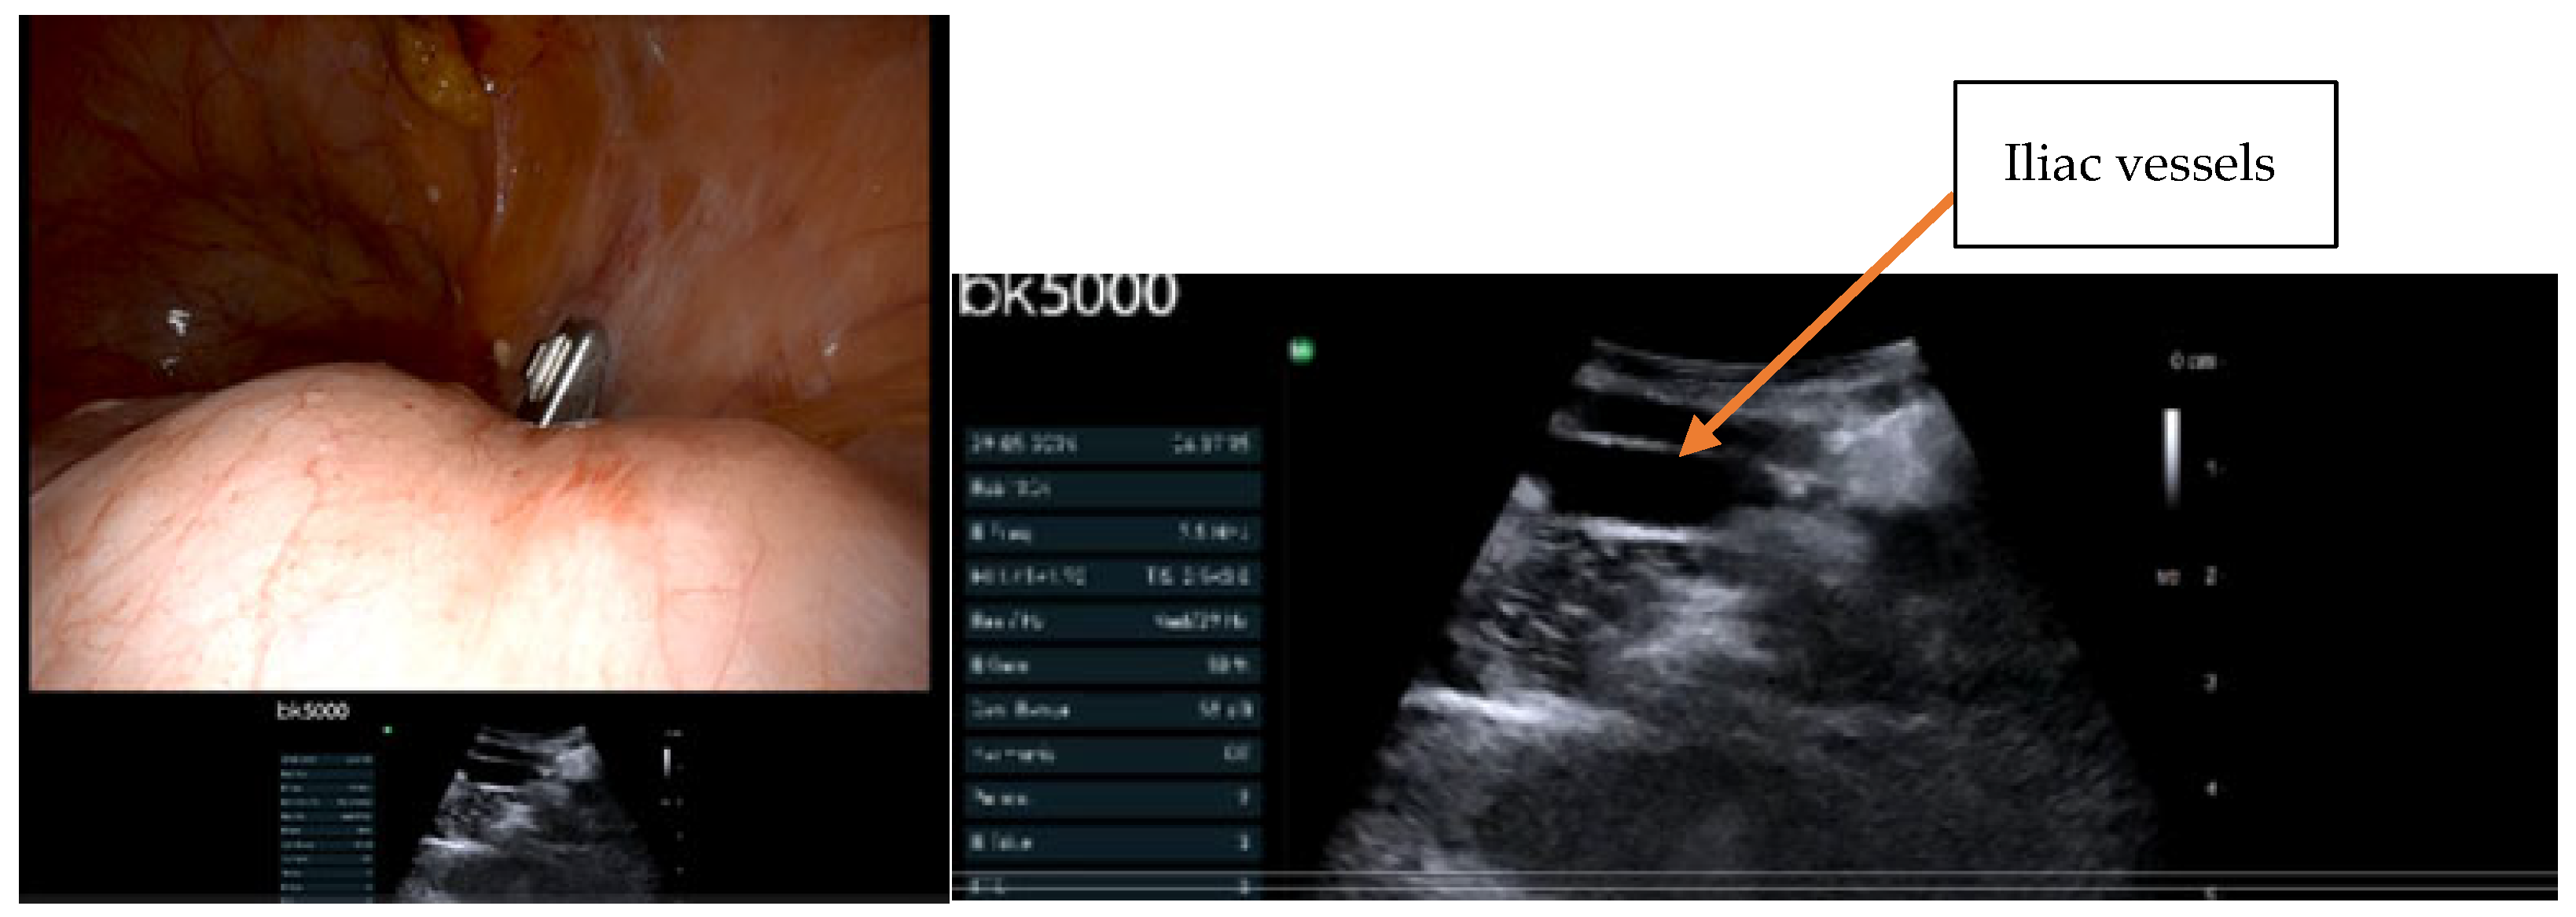

- IOUS in gynecological oncology lymph node assessment and staging

- Real-time confirmation of suspicious nodes before excision

- Precise needle guidance for targeted biopsy

- Immediate assessment of resection completeness

- Identification of critical vascular relationships to prevent injury